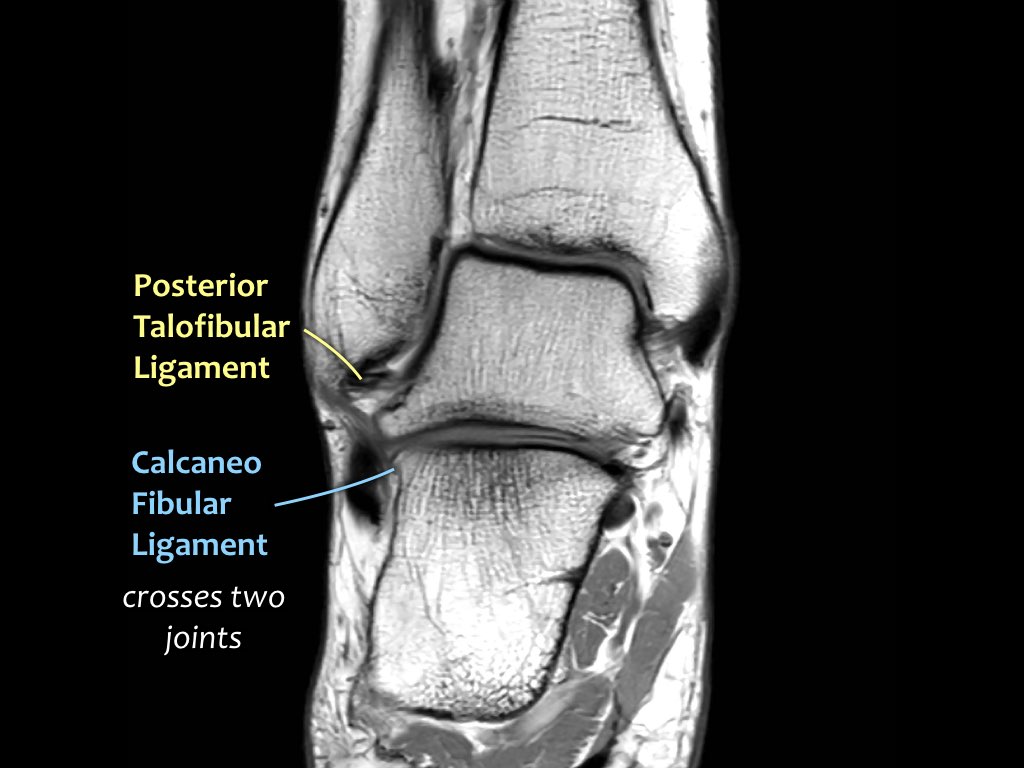

ATFL

Có ba dây chằng ở phía ngoài:

- Dây chằng sên mác trước (anterior talofibular ligament – ATFL)

- Dây chằng gót mác (calcaneofibular ligament – CFL)

- Dây chằng sên mác sau (posterior talofibular ligament – PTFL).

Dây chằng ATFL chạy từ mắt cá ngoài ra phía trước đến bờ ngoài của xương sên.

Dây chằng này có hướng nằm ngang và được quan sát rõ nhất trên ảnh cắt ngang.

Đây là dây chằng bị tổn thương thường gặp nhất ở cổ chân và cũng là dây chằng đầu tiên bị tổn thương ở phía ngoài.

Điều này có nghĩa là khi dây chằng CFL hoặc PTFL bị tổn thương, rất có khả năng dây chằng ATFL cũng đã bị tổn thương.